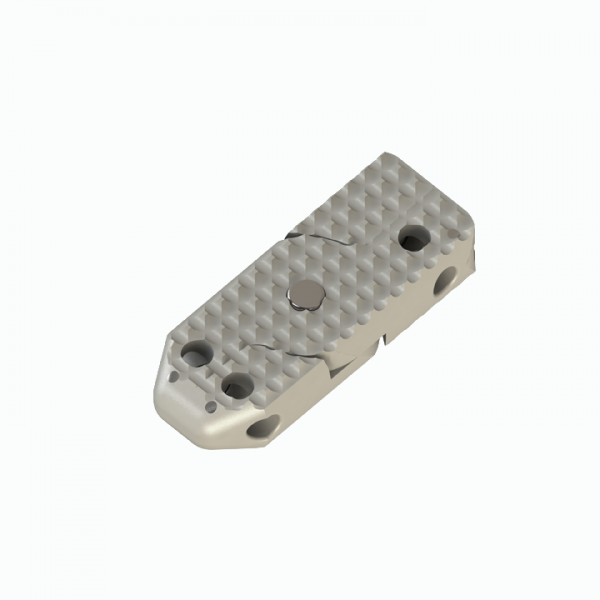

Aditus Lumbar Xlif Cage

- Anatomical Design

- PEEK Material and TI-6AL-4V ELI ( ISO 5832-3 )

- Titanium Alloy Material

- Titanium Pin Indicators for Radiological Imaging

- Special Thread Structure Providing Strong Adhesion at Surfaces of its Endplates

- Easy to Place within Disc Distance and Thanks to Elliptical Front Design

- Applicability of Posterior, Posterior Lateral or Extra Lateral from Disc Distance

- Functionality Leverage from 5 Points for Axial Loading Simple Implantation